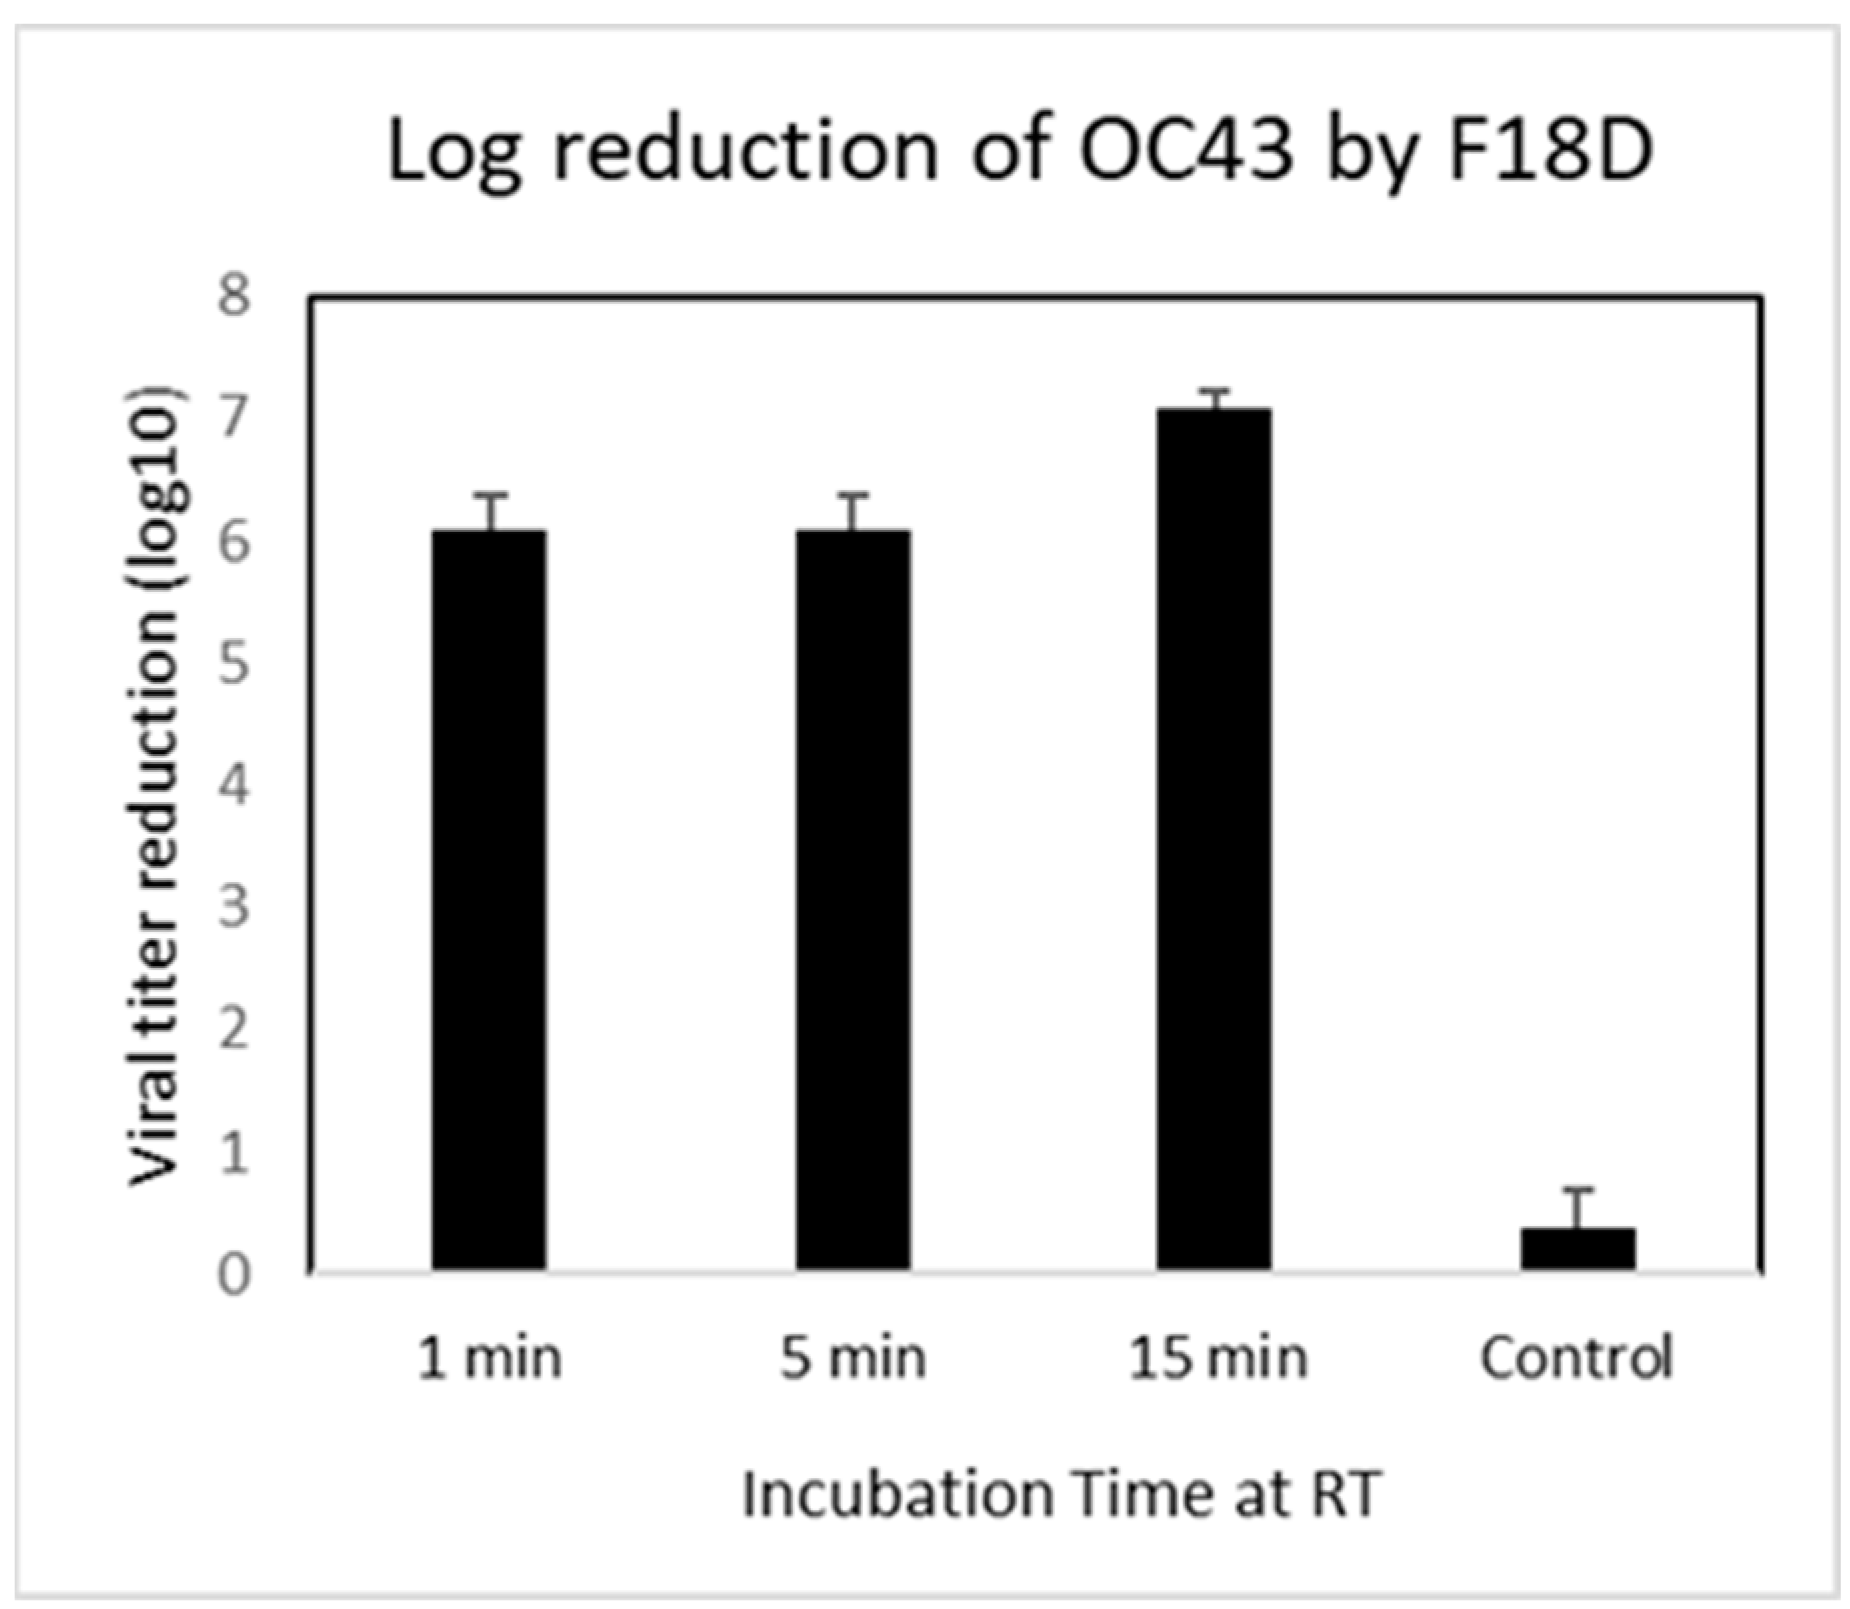

3.2. Contact Inhibition

3.3. Transmission Electron Microscopy (TEM) Imaging of F18D-Treated Virus